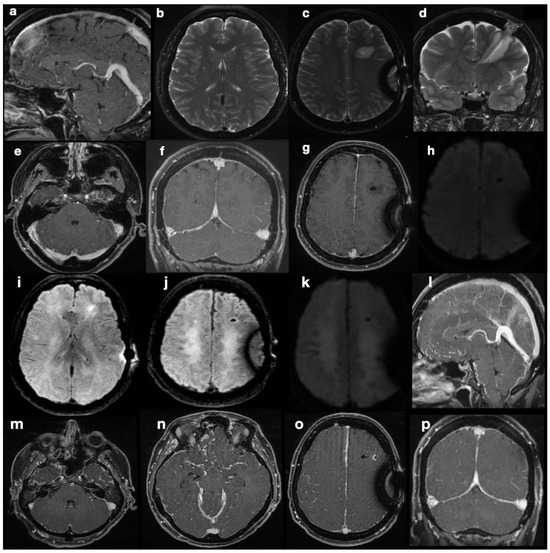

Five months after shunting, continuous and sharp cephalgia arose; MR scans revealed findings suggestive of intracranial hypotension, possibly due to overdrainage (Figure 2a–h). The patient was therefore admitted into hospital, and her shunt was equipped with an anti-siphon device. According to the initial suspicion of overshunting, the valve-opening pressure increased to 200 cmH2O, and eventually, the system was mechanically closed. Despite this, during the patient’s stay, she developed progressive visual impairments, aphasia, and motor incoordination in addition to her pre-existing symptoms, culminating in sensory obnubilation. A few weeks later, a further MR scan showed diffuse demyelination-like alterations of the deep white matter in both hemispheres, along with findings still suggestive of intracranial hypotension, such as collapsed ventricles, dural thickening at the vertex, small sulci, turgidity of dural venous sinuses and brain superficial veins (Figure 2i–p). Insertion of a catheter for ICP monitoring revealed marked intracranial hypertension (50 mmHg). A posteriori evaluation of MR images could not identify any secondary cause of intracranial hypertension. Direct causes of the observed visual impairments were excluded based on MRI examinations, which were persistently negative for optic pathway disease.

Since no MRI sign of intra-cranial hypertension was visible in this examination, the increased ICP found at the time of the new catheter insertion was surprising. The coexistence of collapsed appearance of the lateral ventricles and evidence of correct shunt functioning without overdrainage led to the diagnosis of slit ventricle syndrome. An emergency decompressive craniectomy could not prevent the patient’s death.

Pathophysiological explanations of this condition encompass concurrent mechanisms, such as shunt overdrainage, compensatory venous congestion (as we documented in our case, Figure 2f–h), and altered compliance of the ventricular system and cerebral tissue [8]. In patients with shunt-associated headache, therapeutic management is traditionally based on migraine medication [10] and diuretics [11]. Refractory cases were classified by Panagopoulos et al. [8] into two categories: headache due to intracranial hypotension (overdrainage) and pathological compliance of the ventricular system (classical SVS). In our case, ambiguous MRI findings led to the misclassification of patients in the former category when they actually belonged to the latter. Reduced ventricular compliance masked the diagnosis of intracranial hypertension and favored the misdiagnosis of hypotension. The correct diagnosis of SVS led us to reactivate the shunting device and, eventually, perform a decompressive craniectomy, but this was not timely enough to stop the symptom progression. Notably, the physiology of CSF intra- and extra-ventricular circulation was preserved. Orthodromic circulation was present from the choroid plexus in the ventricles to the arachnoid granulations, without obstructive phenomena at any stage. CSF shunting was necessary to counteract intracranial pressure increase, worsened by reduced ventricular wall compliance. The treatments we performed included all of the widely accepted recommendations for headache due to intracranial hypotension, namely: (1) the addition of an anti-siphon device; (2) an increase in valve opening pressure; (3) a combination of both in refractory cases; and (4) careful check of the ventricular catheter and replacement in cases of obstruction [8]. Treatment of proper SVS, with pathological compliance of the ventricular system, is more controversial. Proposed interventions are highly heterogeneous and include shunt revision/repositioning/substitution, third ventriculostomy, an increase in valve opening pressure, and decompressive surgery [8,12]. This is because appropriate treatment should be provided according to the underlying pathophysiological context, not the epiphenomenon of altered ventricular compliance. Endoscopic third ventriculostomy can be appropriate in cases of raised ICP and obstructive hydrocephalus; shunt revision when obstruction is exacerbating ICP increase in combination with altered ventricular compliance; and increase in valve opening pressure in shunted children where dampened CSF pressure waves have induced abnormal calvarial synostosis [13]. Further research is needed to clarify the emerging role of the glymphatic system in IIH pathogenesis [14,15] in order to propose less invasive and disease-modifying treatments. To the best of our knowledge, no medical treatment targeting aquaporin-4 changes or neurogliovascular unit disruption in IIH has ever been developed, currently leaving no alternatives to surgical treatments—and complications.

Figure 2. Post-shunting MRI scans. The first post-operative MRI (ah) is highly suggestive of intracranial hypotension, with “slumping midbrain” and depression of the vena magna Galeni (a), small ventricles (b), and supra- and sub-tentorial dural thickening with turgidity of the venous sinuses (fh). At the same time, a fluid effusion surrounds the parenchymal course of the catheter, hinting at draining dysfunction. DWI sequences did not show abnormal findings (e). MR scan after marked neurological deterioration (ip) shows ongoing demyelination of deep periventricular white matter in both hemispheres (ik). Radiological signs suggestive of intra-cranial hypotension are even more conspicuous here than previously described in images (ah).